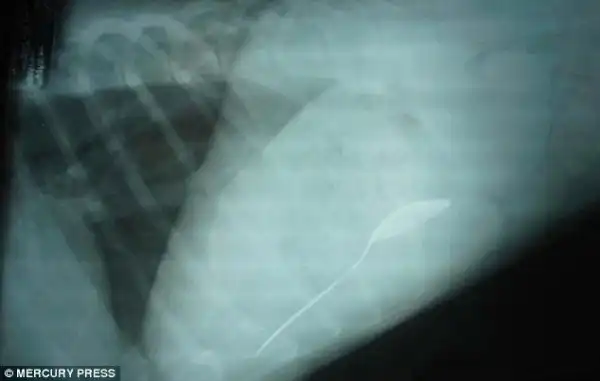

Бездомный щенок лабрадора, который умудрился каким-то образом проглотить удочку

Вот она и сам щенок